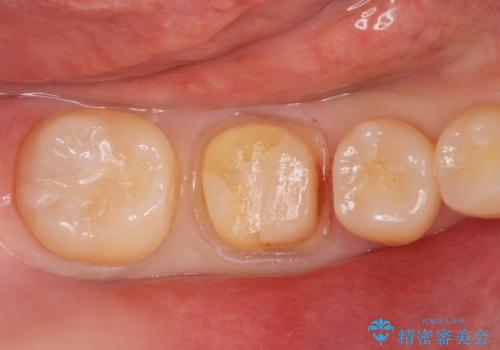

食べ物食べたら歯が欠けた。

- 過去に退院で治療した詰め物が欠けたことにより来院。

古いプラスチックの樹脂、虫歯を全て取り除き

ジルコニアクラウンにて治療しました。

プラスチックの樹脂(CR)の治療は保険適応で白くて一日で

治療が終わるため安価であり、患者様の負担が少ない治療ですが

プラスチック樹脂は経年劣化して茶色くなります。

また耐久性もジルコニアクラウンに比べて低く、割れてしまうことがあります。